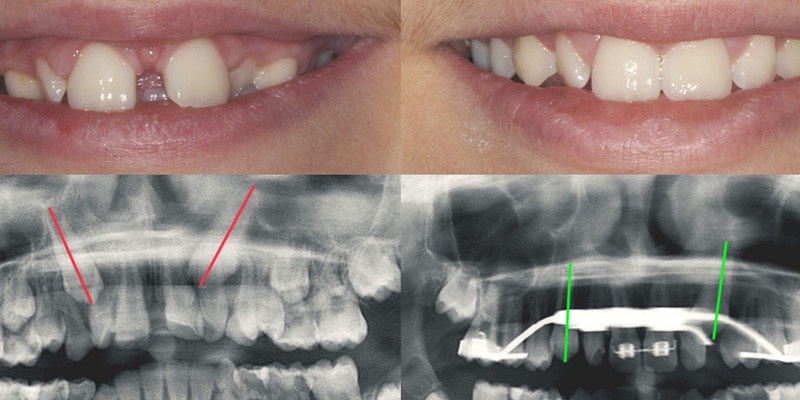

The treatment of palatally displaced impacted canines is often challenging. It is best to never have to mechanically erupt a maxillary canine, but rather to obtain an autonomous eruption. Nevertheless, dealing with young patients and their parents, deciding how and when to intervene are often an hassle. In this webinar I'll share with you my clinical experience and my knolwedge of the existing literature on this topic. At the end of this lecture, you'll be confident in approaching any case of displaced maxillary canines.